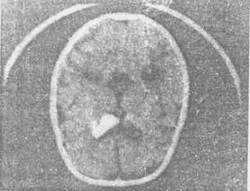

Были идентифицированы субэпендимальные гигантоклеточные образования (СГО). Относительную редкость обнаружения такого рода изменений у детей можно объяснить их медленным ростом — пика визуализации они достигают при возрасте пациента более 11 — 13 лет. Основное отличие СГО от субэпендимальных узлов состоит не в их морфологической структуре, aвразмерах (они всегда существенно превышают размеры субэпендимальных узлов) и, самое главное, в тенденции к постепенному увеличению. Можно предположить, что СГО — это по сути те же субэпендимальные узлы, клетки которых по неясной причине не утратили способности к репродукции. Считается, что СГО выявляются примерно в 10-15% случаев ТС.Как и субэпендимальные узлы, СГО локализуются преимущественно вокруг отверстия Монро, при этом часто деформируя его и приводя к разбитию вторичной обструктивной гидроцефалии (рис. 1).

Рис. 1.

Компьютерная томограмма головного мозга, аксиальный срез на уровне передних рогов боковых желудочков: массивное калкальцинированное опухолевидное образование, практически полностью обтурирующее передний рог правого бокового желудочка.